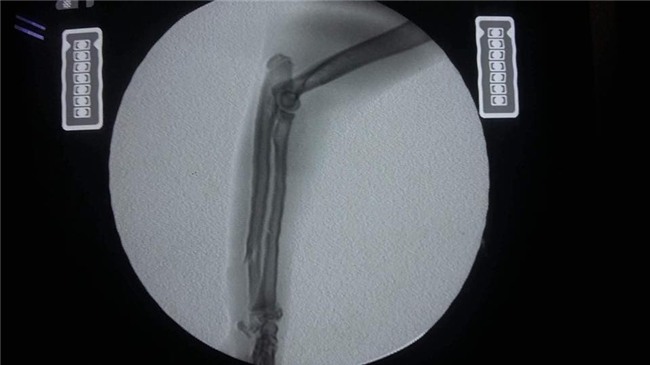

Bé mèo tên là Xù đang được nằm điều trị tại bệnh viện thú y IVET Lạc Long Quân. Bây giờ, bé đang bị liệt nửa người nên chỉ được truyền dịch và thông tiểu. Vì bị thương rất nặng nên bé phải nằm viện 2 đến 3 ngày nữa để hồi phục sức khỏe mới có thể phẫu thuật được.

May mắn là đã có một bệnh viện đồng ý chữa trị nhưng phải mời bác sỹ từ Thái Lan qua để giải phẫu. Chi phí cho 1 ngày điều tri tại viện là 1,4 triệu đồng và phải nằm khoảng 10 ngày. Chi phí mổ hàm của chú mèo là 2 triệu đồng trong khi phí phẫu thuật điều trị cột sống và thần kinh là 25 triệu đồng. Toàn bộ chi phí phẫu thuật và tiền viện phí lên đến hơn 40 triệu.